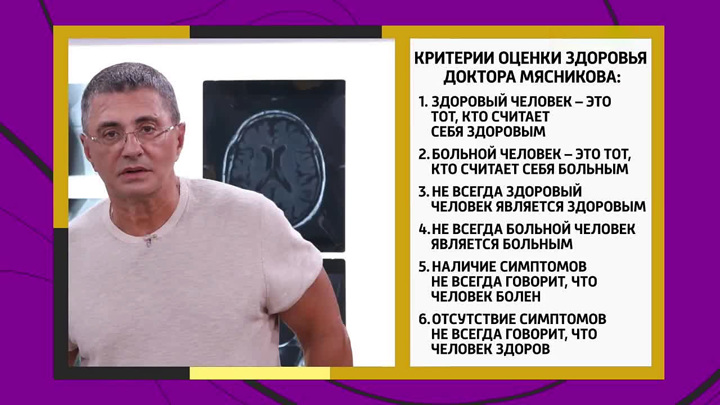

Шесть принципов опытного доктора Мясникова: здоровый человек – это тот, кто считает себя здоровым. А больной человек – тот, кто считает себя больным. При этом, далеко не всегда здоровый человек является здоровым. И далеко не всегда больной человек является больным. Наличие симптомов не всегда говорит о том, что ты больной. А отсутствие симптомов не всегда говорит, что ты – здоровый.

Шесть принципов опытного доктора Мясникова: здоровый человек – это тот, кто считает себя здоровым. А больной человек – тот, кто считает себя больным. При этом, далеко не всегда здоровый человек является здоровым. И далеко не всегда больной человек является больным. Наличие симптомов не всегда говорит о том, что ты больной. А отсутствие симптомов не всегда говорит, что ты – здоровый.